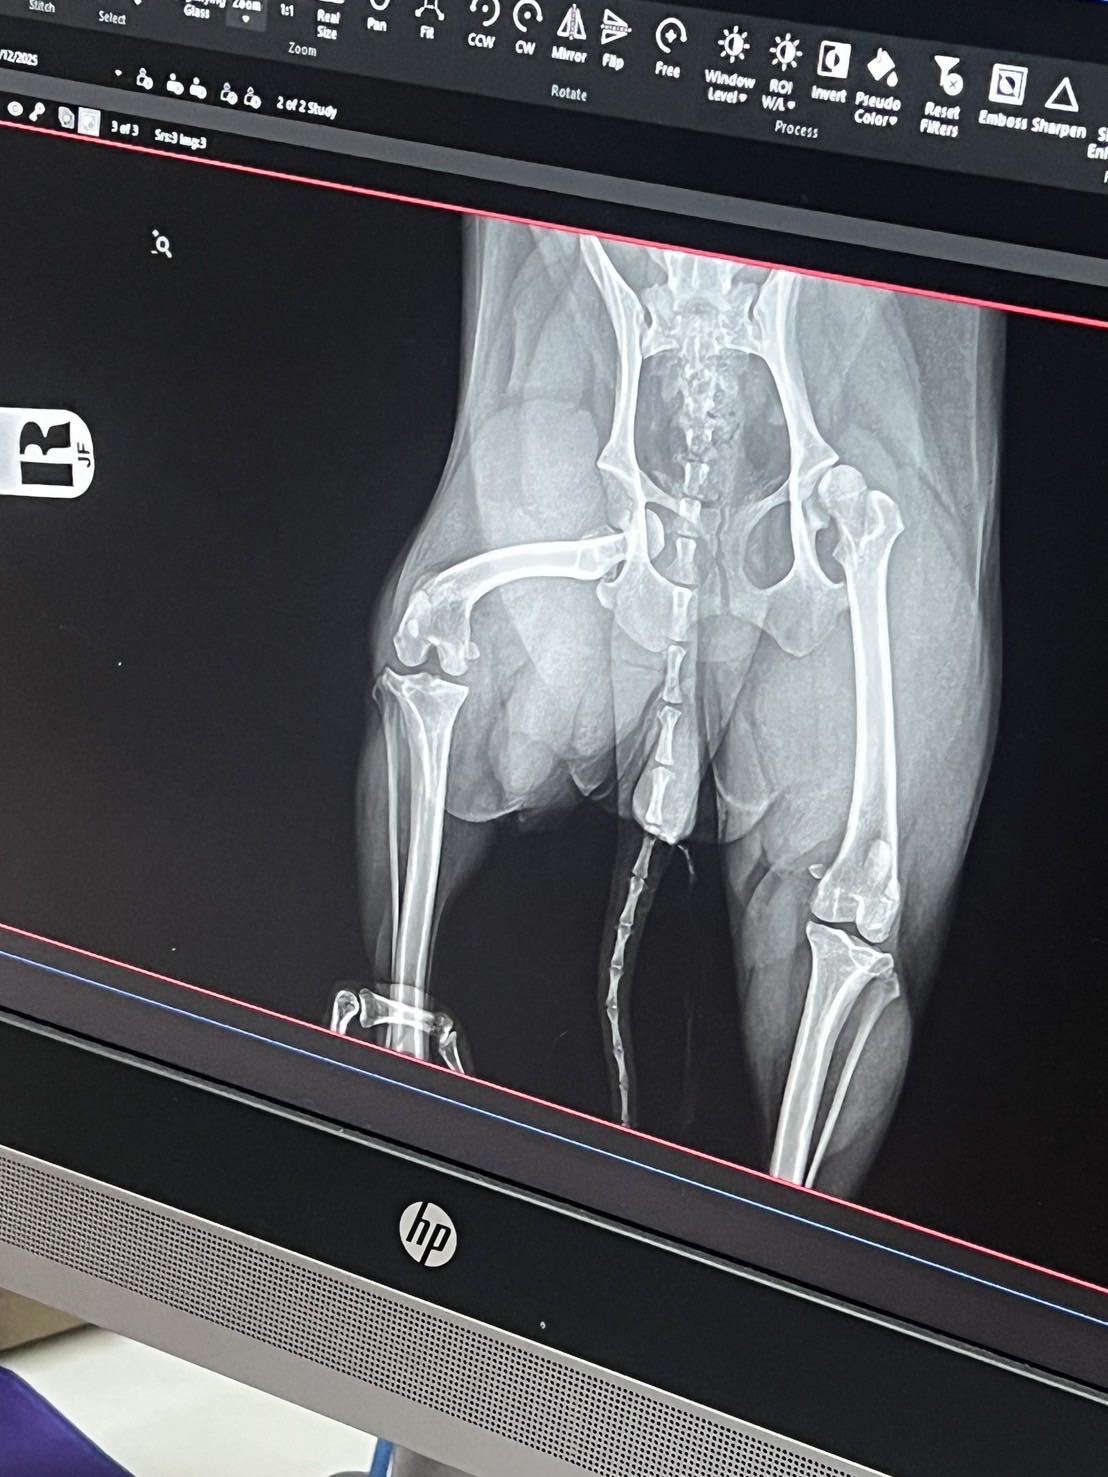

น้องหมากระดูกสะโพกขวาหลุดค่ะ เลยอยากให้ช่วยแนะนำ รพ ผ่าตัดให้หน่อยค่ะ อยู่ กทม สมุทรปราการ หรือ ปริมณฑลได้หมดค่ะ น้องพึ่งเป็นช่วง 14.00 ของวันนี้ค่ะ (26/12)

แนะนำ รพ.ผ่ทนตัดกระดูกสุนัขให้หน่อยค่ะ